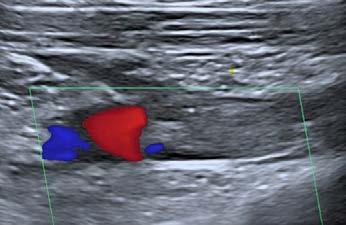

El día 18/2/2022 el paciente refiere dolor torácico. Se realiza un electrocardiograma, que muestra elevación del segmento ST en las derivaciones anteriores en relación con un infarto agudo de miocardio (IAM) anterior. Se activa código infarto y se realiza una coronariografía emergente, que muestra una oclusión de perfil embólico en la arteria descendente anterior media (Figura 1, flecha amarilla). Se trata con trombectomía aspirativa con buen resultado angiográfico final con flujo TIMI 3. Se inicia tratamiento con perfusión de heparina sódica. El día 19/2 el paciente comienza con cefalea muy intensa y afasia, por lo que se activa nuevamente código ictus y se realiza un angioTAC craneal que muestra una hemorragia subaracnoidea (HSA) de predominio izquierdo secundaria a sangrado por un aneurisma disecante de la rama M2 de la arteria cerebral media izquierda (Figura 2, flecha amarilla). Se decide completar estudio con una angiografía que confirma los hallazgos del TAC. Por el alto riesgo de resangrado y la necesidad de anticoagulación oral permanente, se decide embolización del aneurisma con coils, que resulta exitoso (Figura 3, flecha amarilla). Se reinicia durante el ingreso perfusión de heparina sódica y unos días antes del alta se comienza con anticoagulación oral con apixaban 5 mg/12 horas. La evolución clínica es favorable, siendo la exploración física al alta normal. Tras tres años de seguimiento bajo tratamiento con apixaban 5 mg/12 horas no han sido reportados nuevos episodios de sangrado ni de trombosis.